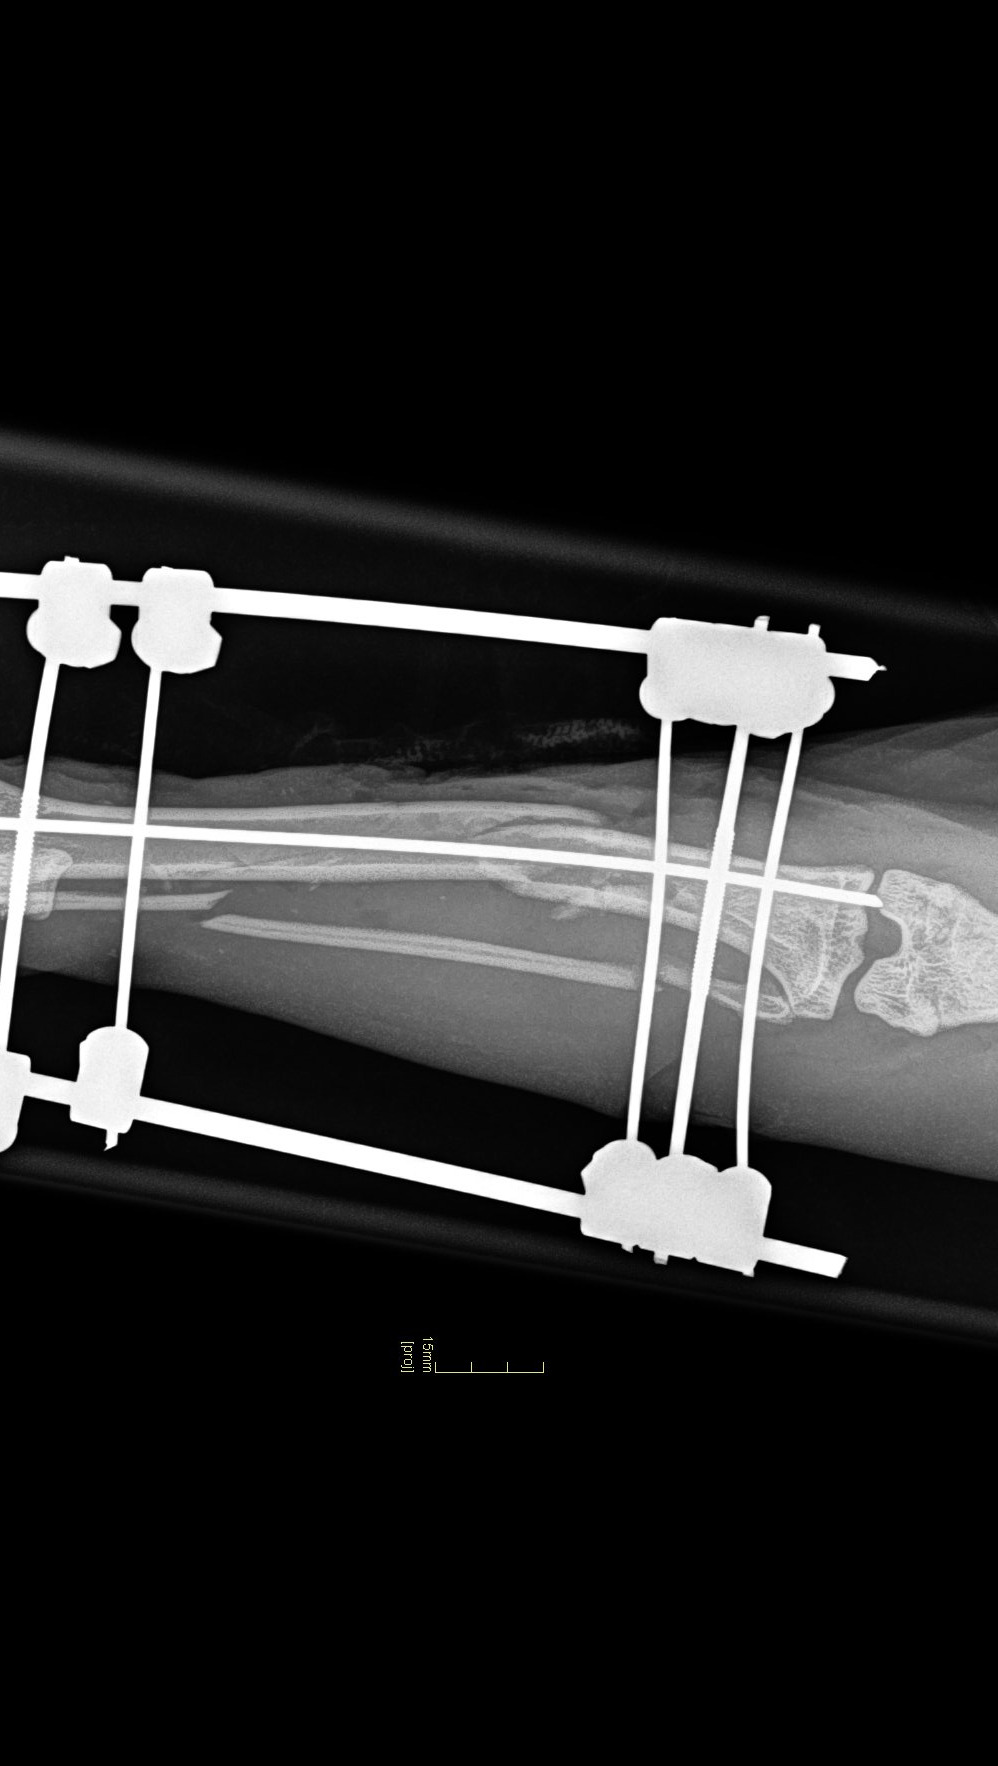

Inmiddels heeft hij deze operatie ondergaan en heeft nu een externe fixatie door zijn botten heen om het te laten genezen.

He has now undergone this surgery and now has an external fixation through his bones to allow it to heal.